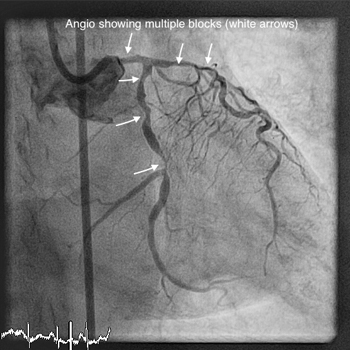

Bifurcation stenting

Learn more